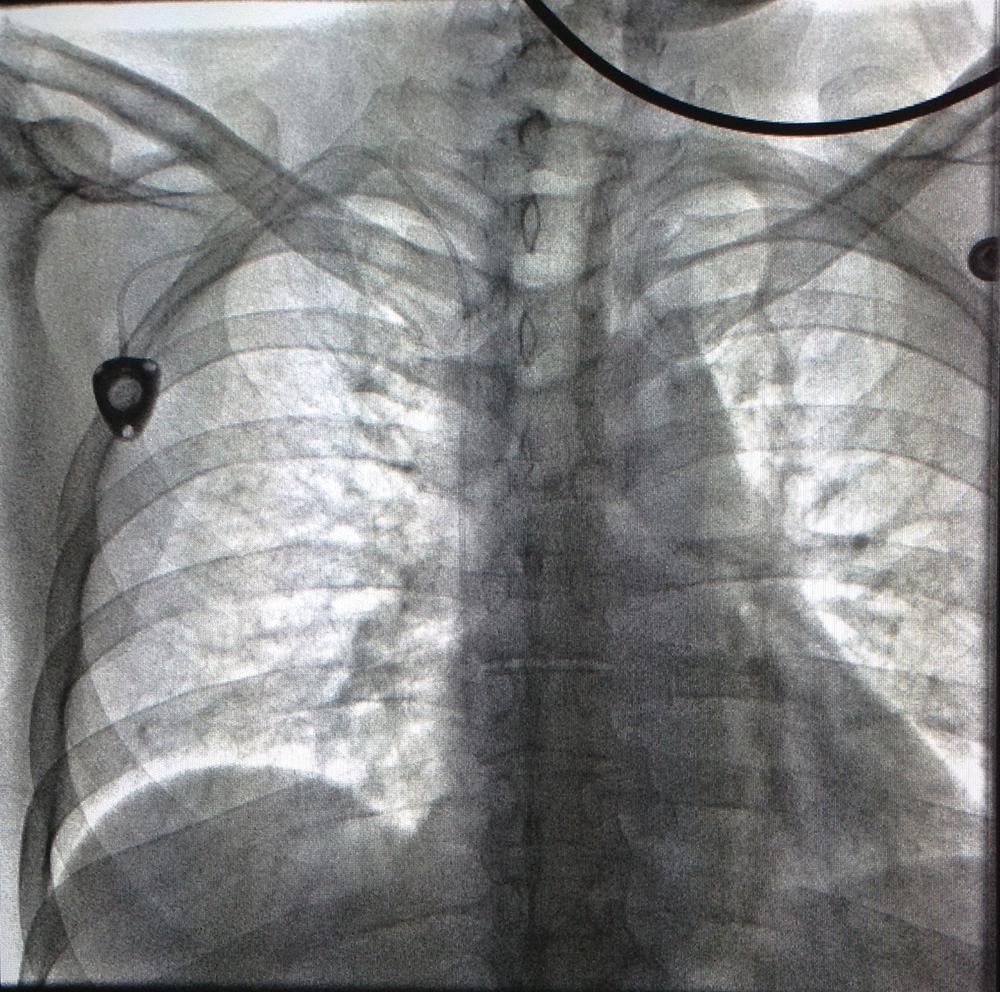

3. Chest x-ray rotation tissues: Not infrequently, the chest x-ray will be rotated causing the right cardiac margin to deviate from its normal AP appearance. In such situations, depending on the degree of rotation, an estimation of the SWEET SPOT™ is all that may be possible. In such circumstances, the right cardiophrenic angle is the most reliable anatomic landmark. Since the right atrium is immediately cephalad to a normally positioned right cardiophrenic angle, a reliable estimation of acceptable catheter tip location is still possible. The height, and consequently the width of the rectangular Sweet Spot™ box will be less exact and therefore a relatively short catheter tip position may require a non- rotated chest x-ray to confirm an acceptable location. Aim for the right atrium. See Figs. T.1, T.2, and T.3.

6. Assessment of normal position of right cardiophrenic angle: The best way to confirm a normally positioned right cardiophrenic angle is to look at the left cardiophrenic angle. Generally speaking, the right cardiophrenic angle should be at approximately the same height as the left cardiophrenic angle. In the case of an elevated right cardiophrenic angle, experience and a solid understanding of SWEET SPOT™ anatomy may suffice. However with very low lung volumes and bilaterally raised hemi-diaphrams, even this may not be sufficient. See Fig. # 8.

15. The right margin of the high density cardiomediastinal silhouette is normally seen when low density aerated right lung is adjacent to it. Any process of soft tissue density that is situated at that margin will obscure that margin – proportional to its size. Common examples are pneumonia, atelectasis, tumor & pleural effusion. See Fig.# 26 - Gallery. Also see slide #46 of AVA Presentation.